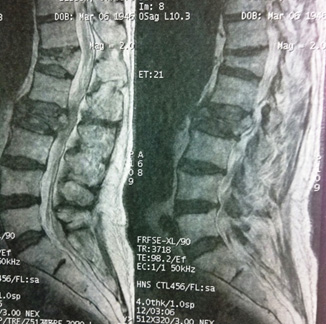

Au-dessus de T4

Dr Jacques Fechtenbaum Hôpital Cochin - Paris

Mr D. est né le 24 mars 1934. Il est suivi et traité pour un cancer des intestins et des métastases pulmonaires. Il vient vous consulter pour des cervicalgies hautes avec ébauche de névralgie d’Arnold.

Ces douleurs sont d’horaire inflammatoire. Vous évoquez le diagnostic de métastases osseuses et vous demandez d’emblée une IRM du rachis cervical.

L’IRM confirme le diagnostic de métastases ostéolytiques de C2 avec un hypersignal T2 rehaussé après